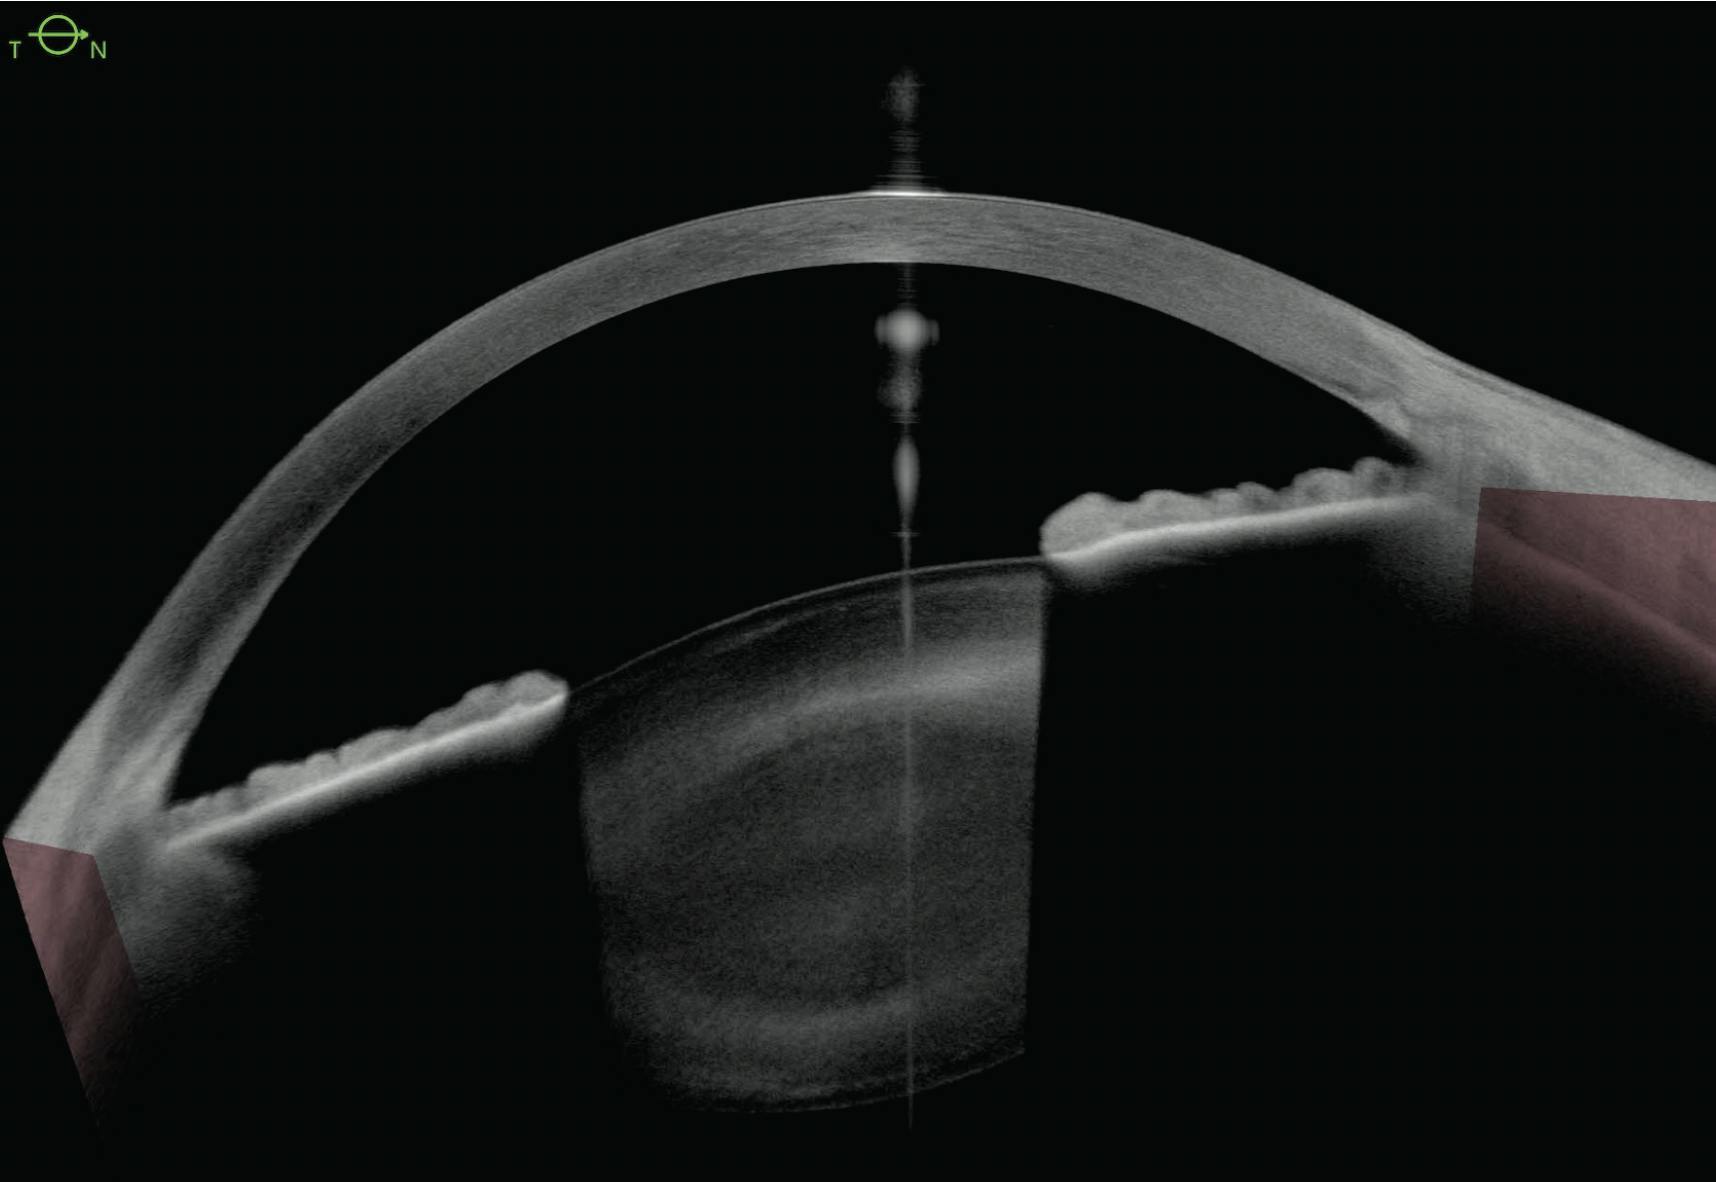

Visual field testing shows severe constriction, with fixation affected in all four quadrants and no remaining pattern deviation (Figure 2). OCT imaging is unreliable owing to signal loss and peripapillary atrophy. Anterior segment OCT confirms the absence of posterior iris bowing (Figure 3). Ultrasound biomicroscopy reveals moderate diffuse zonulopathy.